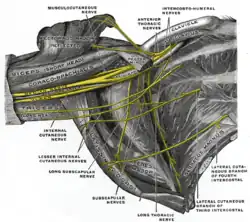

O plexo braquial direito na fossa axilar; visto de frente e por baixo.

O plexo braquial direito na fossa axilar; visto de frente e por baixo. -